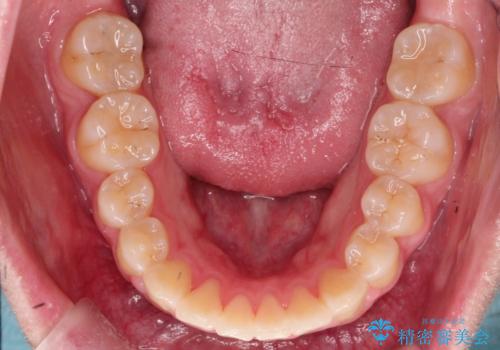

【インビザライン】前歯の凸凹を非抜歯で治療

- 前歯の凸凹を主訴の来院されました。

奥歯を後ろの方に移動させるために矯正用のアンカースクリューを使いながら治療をおこないました。

患者さんの都合により、マウスピースの装着時間が不足したため、途中からワイヤーにて治療を行いました。

インビザラインは20時間以上の装着は必要となるため、患者さんによってはワイヤーの方が向いていることがあります。